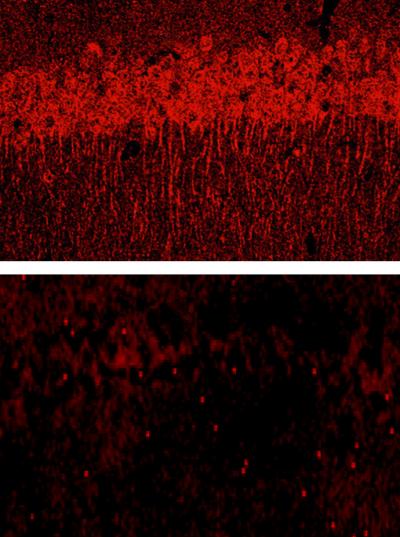

Chen et al. found otherwise when they engineered mice to lack the ECM component laminin in the hippocampus, a brain region often damaged by stroke or injury. If cells languished after parting from the ECM, the researchers reasoned that mice missing laminin would suffer more damage from excitotoxicity. But when excitotoxicity was spurred with an injection of kainate—a molecule that, like glutamate, activates the kainate receptor—the laminin-lacking mice showed less brain damage. After a dose of diced laminin, however, the mutant mice were vulnerable to kainate, indicating that the fragments are the culprit in cell death.

The researchers discovered that chopped-up ECM kills cells by ramping up production of one subunit of the kainate receptor, known as KA1. They speculate that hiking the amount of KA1 subunits might make the receptor more sensitive and thus more likely to trigger an overreaction by the cell.